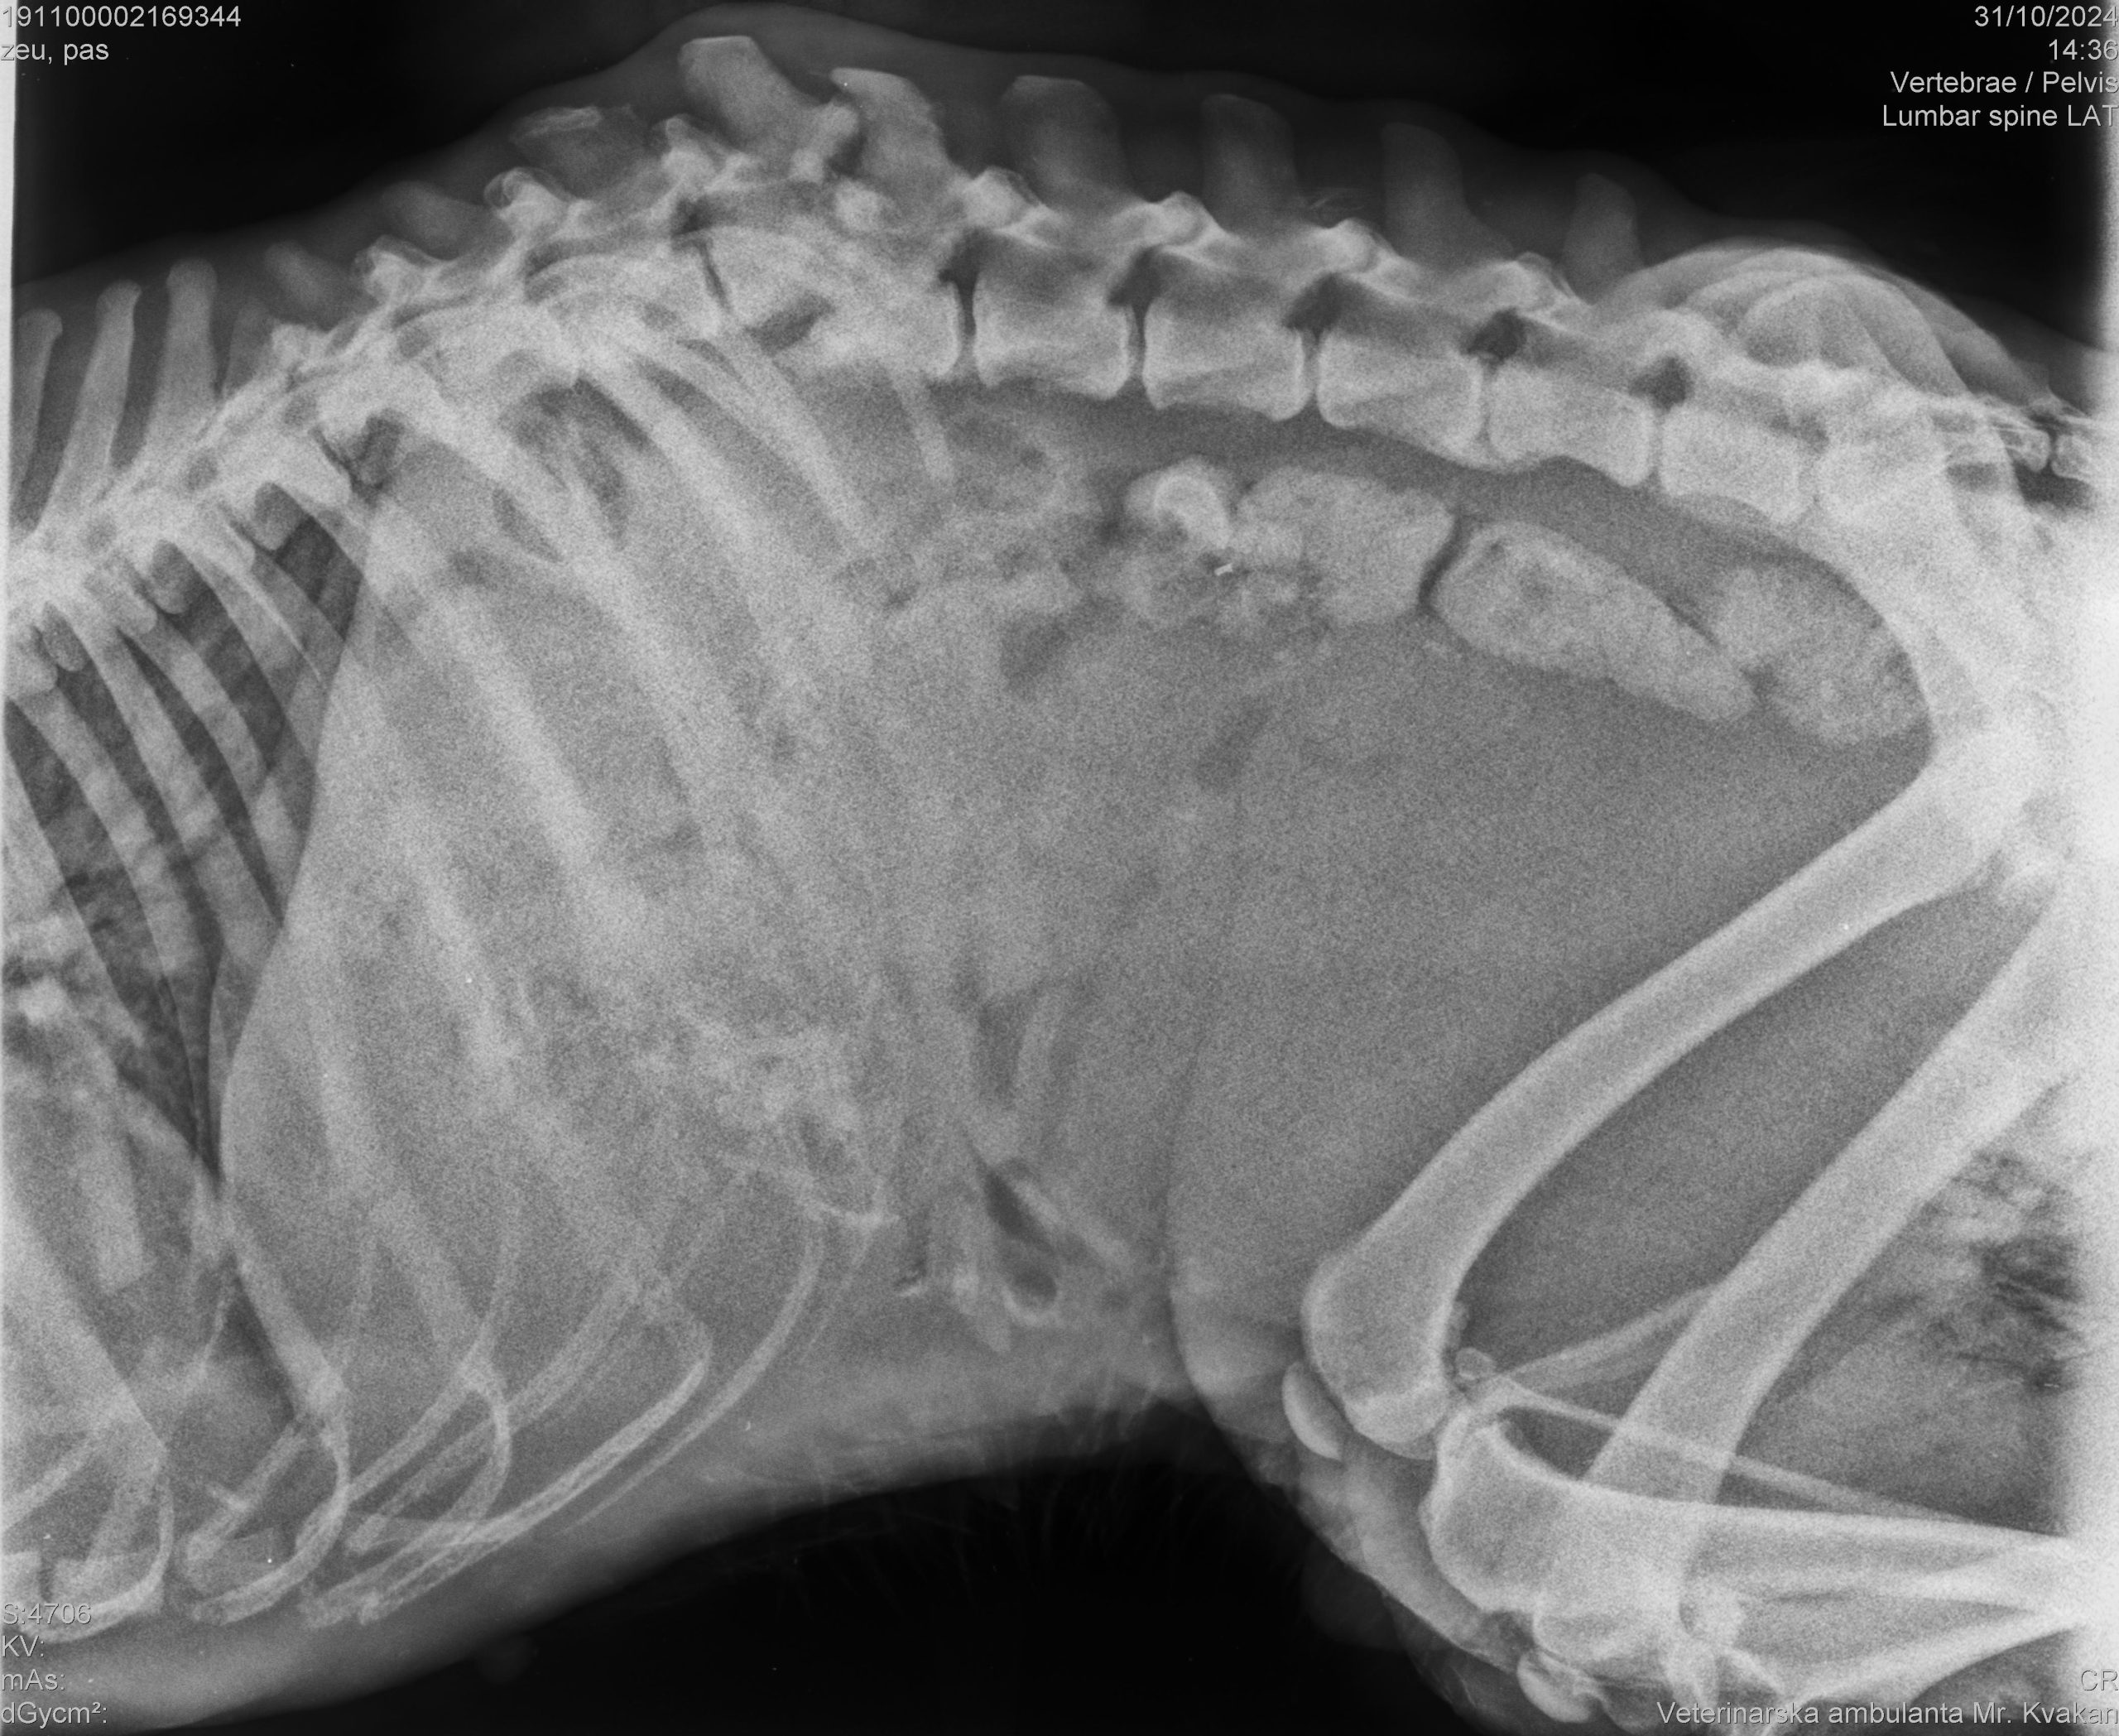

– Pas je označen mikročipom i obrađen u projektu zbrinjavanja pasa u romskim naseljima pod pokroviteljstvom Ministarstva poljoprivrede. Danas su ga do skloništa dovezli stanovnici naselja nakon što se u teškim bolovima i teško povrijeđen (slomljene kralježnice i odrezane noge) vukao po ulici. Zbog teških ozljeda, pas je eutanaziran. Kaznena prijava bit će podnesena DORH-u – rekla je jučer Aleksandra Hampamer iz Skloništa za životinje ‘Prijatelj’ iz Čakovca.